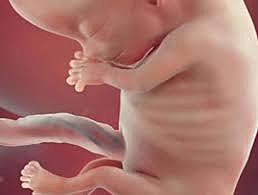

2DO. Mes

Se desarrolla el estomago, el intestino, el hígado y el páncreas. se distinguen los dedos de las manos y pies. se empieza a formar los músculos, los nervios y la médula ósea; se distinguen facciones de la cara, aunque los párpados están cerrados. aparecen los riñones. Succiona el dedo, ahora es un feto.

3ER. Mes

El feto deglute liquido amniótico en cantidades pequeñas, con lo cual practica al acto de deglutir. aparecen los primeros huesos y se diferencia los órganos sexuales. los dedos de las manos y de los pies tienen uñas suaves. los movimientos se intensifican y esto fortalece el vinculo con la madre, todos los órganos del cuerpo maduran y el feto aumenta de peso

4TO Mes

El feto tiene en su piel un vello fino que lo ayuda a conservar el calor. la piel es rosada, transparente y tiene huellas digitales. Se mueve, patea, deglute y puede oír las voces del exterior, fruncir el ceño, hacer muecas y ya cuenta con cuerdas vocales. los bulbos y el nervio olfatorio se forman completamente

5TO. Mes

El cerebro del feto crece 90 grs. cada mes , aproximadamente, lo que permite una mayor maduración de su sistema nervioso, y con ello el fortalecimiento de sus sentidos. el tacto es mas fino y es capaz de sentir diferentes temperatura. su gusto puede diferenciar lo amargo y lo dulce. Puede mover los ojos, duerme y se despierta en intervalos regulares, en esta etapa, el feto crece muy rápido.

6TO Mes

El feto tiene un rostro bien definido, con pestañas y cejas. hace movimientos mas rápidos y explora su entorno y sus propias extremidades. Identifica sonidos, responde a la música y ya puede abrir los ojos. Luce las proporciones que tendrá al nacer

7MO. Mes

En esta etapa maduran los pulmones y el esqueleto, aumentando notablemente el tamaño del feto, por lo cual presiona la vejiga materna. La activación de melanocitos pigmentan los ojos y la piel. El feto se va posicionando para el parto

8VO. Mes

Los pulmones siguen madurando y puede presentar hipo. Los huesos de la cabeza son suaves y flexibles para que el sea m´sa fácil pasar por la vagina. El feto puede patear fuerte. Si naciera en esta etapa, el feto seria prematuro, pero con buenas probabilidades de sobrevivir.

9NO. Mes

Ya puede fabricar sus propias células sanguíneas. Los órganos ya se encuentran bien desarrollados y los pulmones están listos para funcionar por su cuenta. Empieza a descender por el hueco pélvico. Esta a punto de nacer.